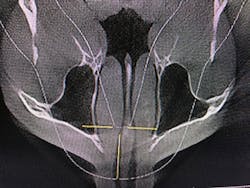

Figure 8: Deviated nasal septum and narrowed airway

After identifying Danny’s history and evaluating the clinical signs, we moved to screening and testing. We recommended a home sleep test for his airway and breathing problems, as well as a Doppler auscultation and CBCT imaging for the TMD and occlusal issues.

The Doppler auscultation revealed reciprocal click on the left temporomandibular joint. The CBCT revealed normal joint anatomy, nasal airway obstruction with a slight deviated septum, and approximately 95% tonsillar obstruction in the posterior throat region. These findings led us to the conclusion of a positive airway/breathing disorder, with a Piper Stage I right temporomandibular joint and Piper Stage IIIa left temporomandibular joint.